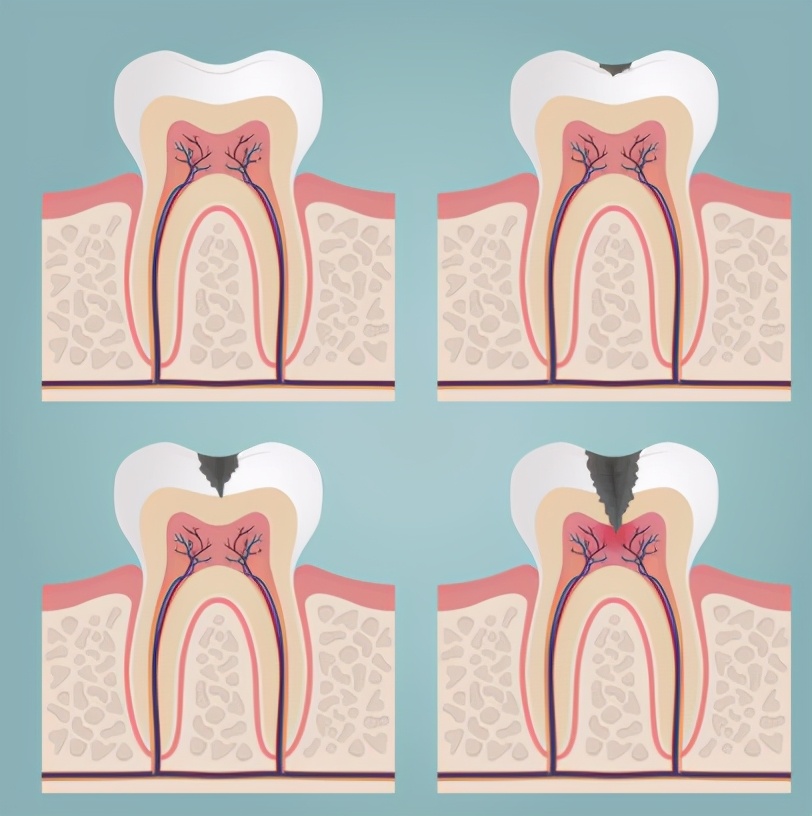

蛀牙主要是由初期的浅龋——中龋——深龋!当蛀牙发展到中或重度的时期,极有可能会诱发牙髓炎、根尖周炎,出现明显疼痛并威胁整颗牙齿。